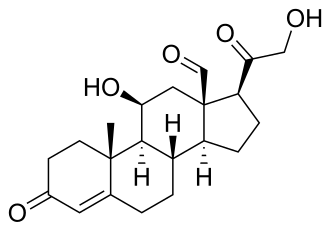

| Aldosterone | |